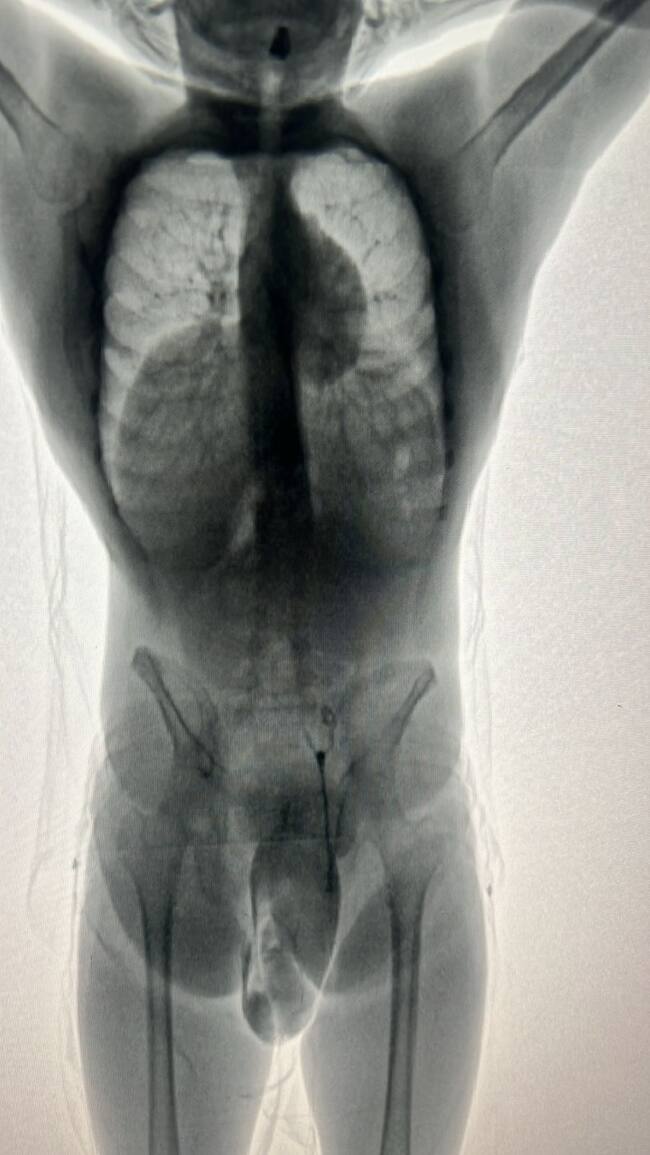

Durante controles desplegados por la Policía Nacional en el abordaje de vuelos nacionales e internacionales, del Aeropuerto Internacional Rafael Núñez capturaron en flagrancia a un joven colombiano que pretendía abordar un vuelo con destino a Santo Domingo, capital de República Dominicana, con más de un kilo de cocaína en sus partes intimas.

“Mediante una revisión que incluyó rayos X se pudo corroborar que el capturado un kilo y ciento noventa gramos del estupefaciente. Con este importante resultado se logra evitar la comercialización de 2.300 dosis de cocaína la cual está avaluada en 12.280 USD, equivalentes a más de $60.000.000 millones”, informó el comandante de la Policía Metropolitana de Cartagena, coronel Yesid Peña.